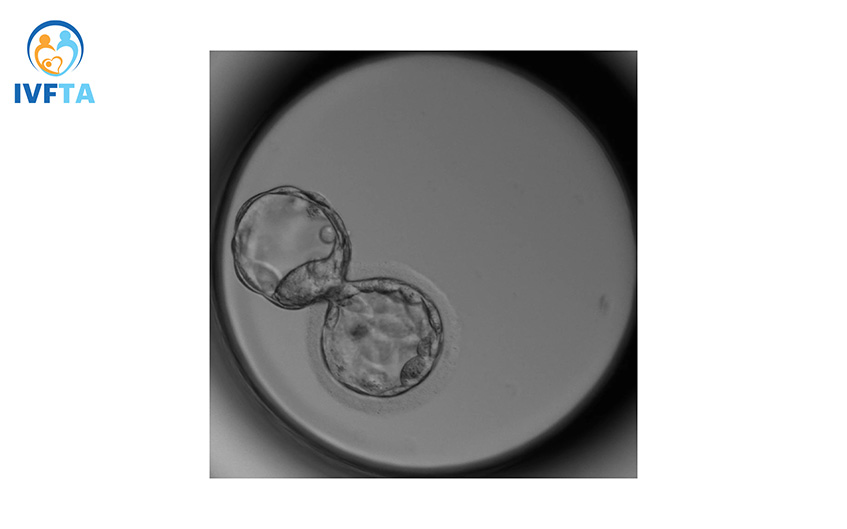

Phôi ngày 5 hay còn gọi là phôi nang có khoảng hơn 200 tế bào, cấu trúc của phôi có hai lớp chính: một lớp tế bào bên trong gọi là tế bào phôi, và lớp bên ngoài gọi là lớp tế bào lá nuôi.

Lựa chọn chuyển phôi vào ngày thứ 5 thay vì ngày thứ 3 (khi phôi là ở giai đoạn phôi phân chia) đã trở thành một xu hướng quan trọng trong lĩnh vực điều trị vô sinh hiếm muộn. Chuyển phôi ngày 5 được cho là có nhiều lợi điểm về quá trình chọn lọc tự nhiên. Chỉ những phôi ngày 3 chất lượng tốt về cả di truyền và hình thái thì mới phát triển tốt ở giai đoạn phôi ngày 5. (1)

Ngược lại, những phôi ngày 3 chất lượng kém hơn thì tiên lượng nuôi lên ngày 5 cũng thấp hơn và tỷ lệ thành công cũng không cao. Phôi ngày 5 cũng được đánh giá giàu sức sống hơn so với ngày 3.